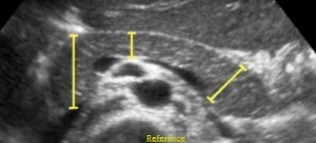

What is the typical AP measurement for the pancreas?

Less than 3 cm

What measurements are these?

What is the normal measurement for these?

AP

Less than 3 cm